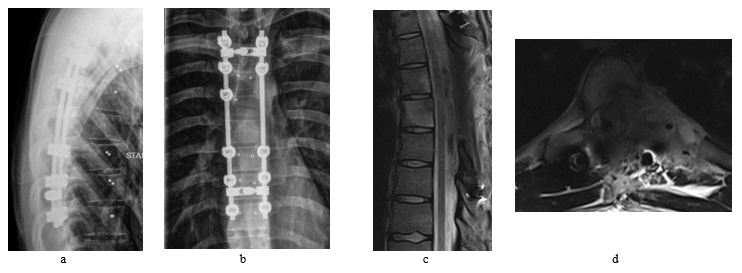

The patient underwent interventional tumor embolization followed the next day by a T4-T10 fusion with posterior decompression and gross total tumor resection. The screws were carbon-based implants and the procedure was carried out with assistance of O-arm, neuromonitoring and a navigation system. Patient had recovered well after the surgery and post-operative MRI revealed a radical resection of the tumor without any complications (Figure 3).

After 3 months of the surgery, follow up MRI scans were performed which had revealed recurrence of the tumor within the surgical bed with further bony destruction and epidural extension (Figure 4). The patient underwent T7 vertebrectomy followed by cage implantation then debulking of the residual tumor via left sided transthoracic approach. Patient has developed high fluid output per chest tube found to be due to CSF leakage which has been treated successfully conservatively, other than that, patient had made smooth recovery.